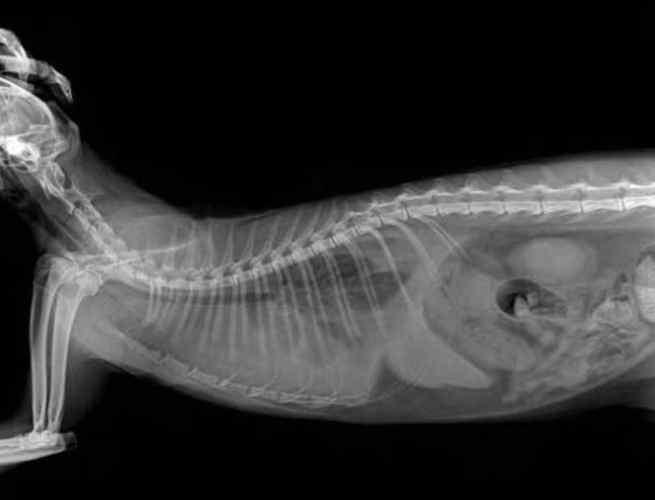

我記得阿福那時就是晚上一直咳,我以為是感冒,結果獸醫用X光一照,肺都白茫茫一片——那是積水的證據。獸醫說,如果早點發現,預後會好很多。所以啊,狗肺積水可以活多久,第一關卡就是你有沒有及時察覺。